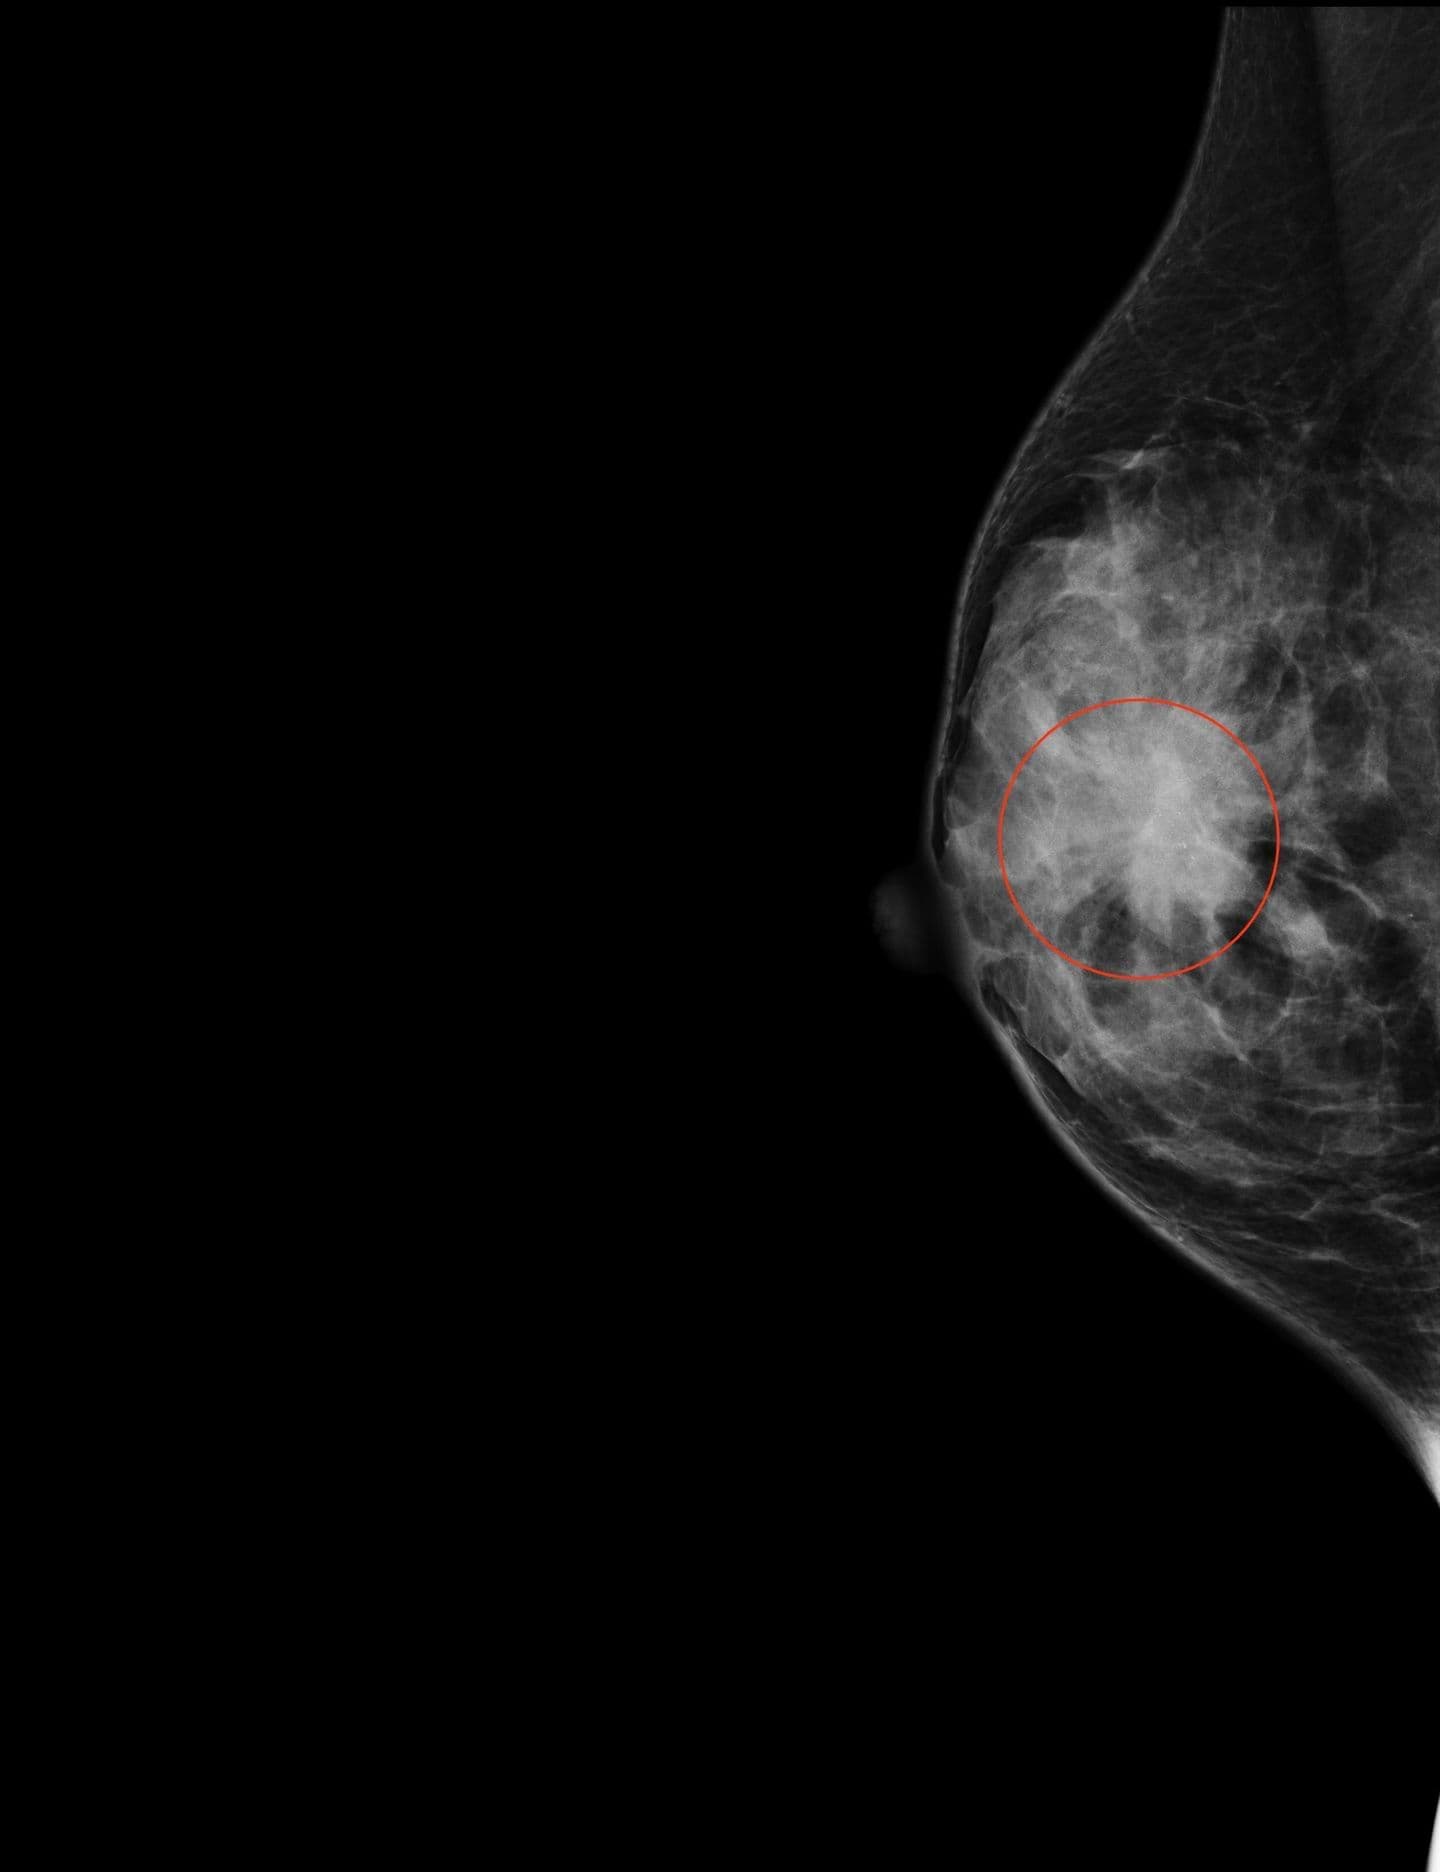

圧迫された乳房を短時間で複数の角度から撮影する三次元撮影技術です。

収集した画像データを1 mm毎のスライスで再構成しているため、従来のマンモグラフィでは乳腺との重なりで見つけにくかった病変を容易に発見することが可能になりました。 また、通常のマンモグラフィと同時に1回の圧迫で撮影できるため、乳房の圧迫による負担が増えることなくより正確な診断が可能です。

マンモグラフィでは分かりづらい病変(赤丸内)が、トモシンセシスによって詳細に観察できます。

トモシンセシスによる三次元画像でより詳しい病変の情報が得られるため、他院で撮影されたことのある方も再度撮影することがあります。